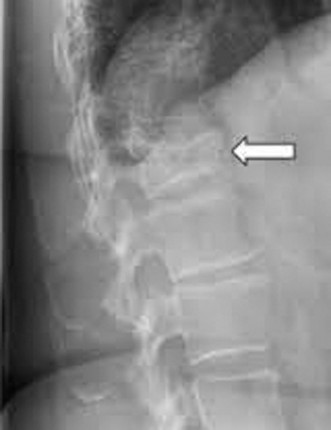

Prognosis of central cord syndrome? Indications for surgery for this disorder? CASE 2 A 56-year-old man presents to you with a chief complaint of severe right buttock, posterior thigh, and lower leg pain for 12 weeks. It radiates to the lateral aspect of his foot, and it is worse with sitting or standing for prolonged periods and with walking. Now over the past 2 weeks, he reports difficulty with toe push-off on the right side. Treatment so far has been nonsteroidal anti-inflammatory drugs (NSAID), physical therapy, and an epidural injection without significant relief. Physical examination findings include 4/5 right ankle plantar flexion, a positive straight leg raise on the right, and an absent right Achilles tendon reflex. Images of his lumbar spine are shown in Figures 1–4 and 1–5.

Figure 1–5

The correct answer is (C). The patient presents with classic right S1 radiculopathy and new onset plantar flexion weakness. The images demonstrate a right-sided paracentral disc herniation at L5/S1 compressing the traversing S1 nerve root. Despite nonoperative management, he continues to have severe pain and new weakness. Continued physical therapy or an epidural injection is unlikely to improve the patient’s pain at this time. In the setting of neurological decline, surgery is more strongly indicated. Lumbar discectomy is the most appropriate procedure for this patient. Fusion would only be indicated if there were radiographic signs of instability, which are not present.